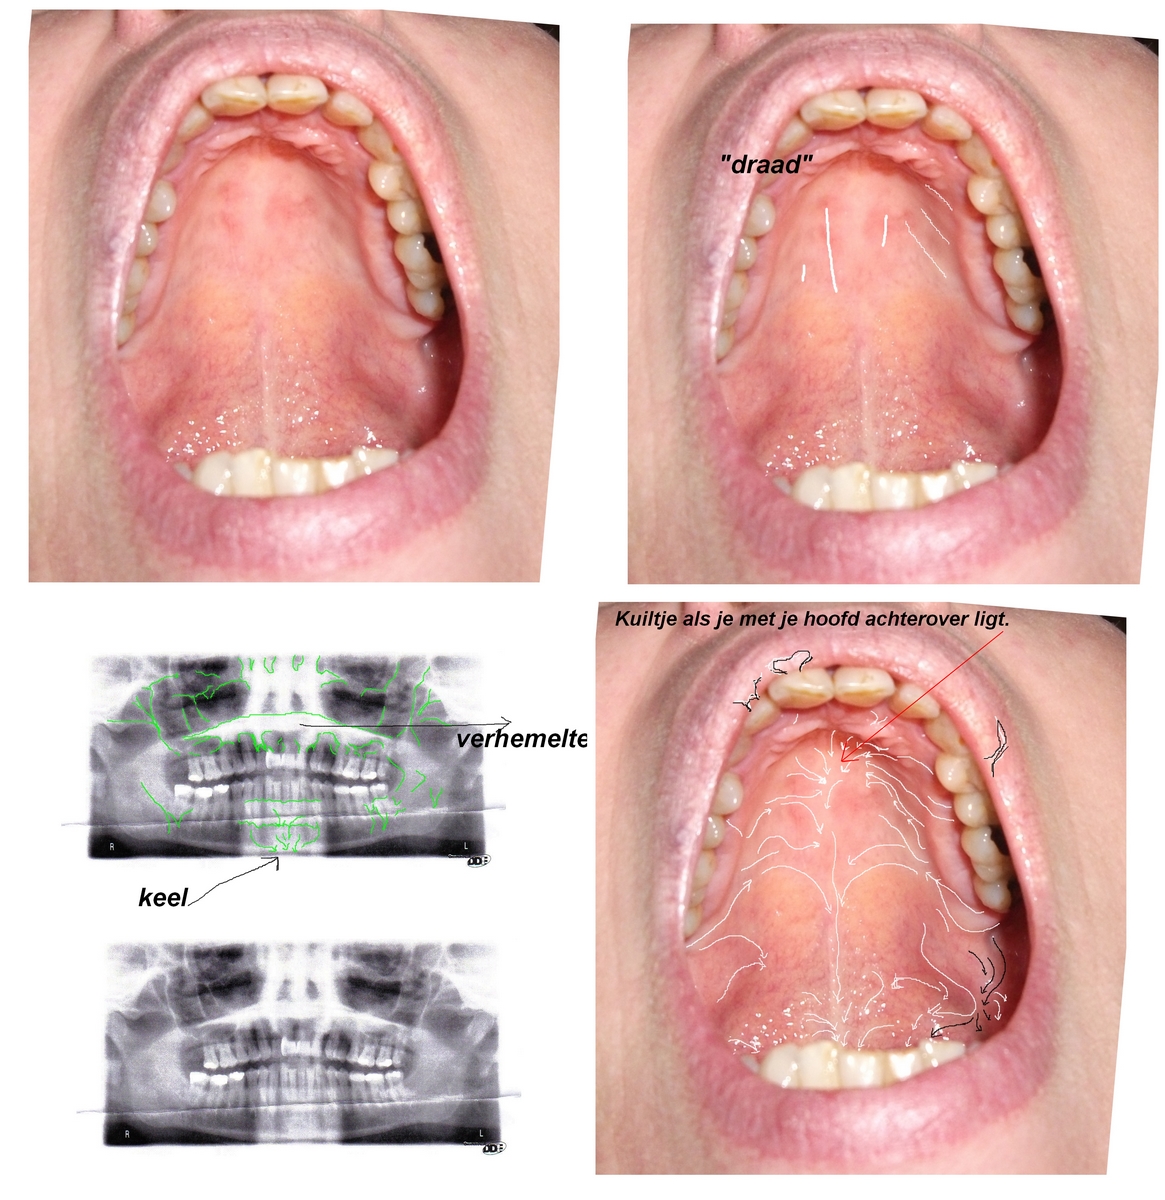

wat op de foto`s staat is al aan materiaal meer dan in welke verpakking bonding dan ook zit. en dat is alleen van nu...

Nu je weer over aerosol begint ga je mijns inziens gewoon maar weer wat roepen om de aandacht terug te krijgen, maar aerosol en kunststof sliertjes.........dat klopt weer niet met je op de foto's ziet. Ik zou bijna zeggen dat je iets hebt opgesnoven omdat het via allerhande zijkanalen van je neusholte naar buiten komt. alleen wat doet die draar op je kin dan weer.

Er is echter niets gebeurd wat lekkage zou kunnen veroorzaken. Ik heb de prothesen ooit gezien en in handen gehad; het omhulsel is behoorlijk dik. Er zou hier echt enorm veel druk op moeten komen te staan of iets doorheen prikken wil het stuk gaan. En niets van dit alles heeft plaats gevonden, de geschiedenis bij de tandarts wel..... Ook zouden de draadjes niet in dat beeld passen, het zou dan zand moeten zijn en dat is er niet. Alleen draadjes in verschillende dikte en lengte.